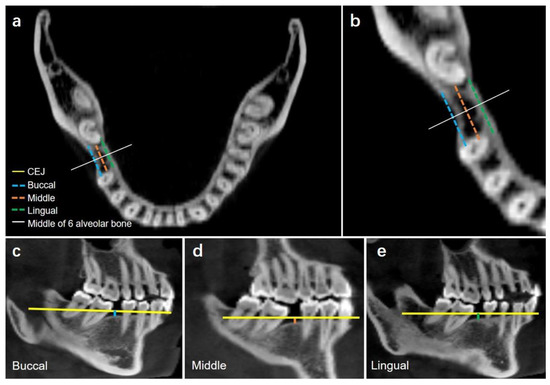

Characteristics of Spatial Changes in Molars and Alveolar Bone Resorption among Patients with Loss of Mandibular First Molars: A CBCT-Based Morphometric Study

Objectives: To investigate the characteristics of spatial changes in molars and alveolar bone resorption among patients with loss of mandibular first molars. Methods: A total of 42 CBCT scans of patients with missing mandibular first molars (3 males, 33 females) and 42 CBCT [...] Read more.

Objectives: To investigate the characteristics of spatial changes in molars and alveolar bone resorption among patients with loss of mandibular first molars. Methods: A total of 42 CBCT scans of patients with missing mandibular first molars (3 males, 33 females) and 42 CBCT scans of control subjects without loss of mandibular first molars (9 males, 27 females) were evaluated in this cross-sectional study. All images were standardized using the mandibular posterior tooth plane with Invivo software. The following indices regarding alveolar bone morphology were measured, including alveolar bone height, bone width, mesiodistal and buccolingual angulation of molars, overeruption of maxillary first molars, bone defects, and the capability of molar mesialization. Results: The vertical alveolar bone height in the missing group was reduced by 1.42 ± 0.70 mm, 1.31 ± 0.68, and 1.46 ± 0.85 mm on the buccal, middle, and lingual side, respectively (no differences among the three sides; p > 0.05). Alveolar bone width was reduced the greatest at the buccal CEJ level and the least at the lingual apex level. Mandibular second molar mesial tipping (with mean of the mesiodistal angulation = 57.47 ± 10.34°) and lingual tipping (with mean of the buccolingual angulation = 71.75 ± 8.34°) were observed. The mesial and distal cusps of maxillary first molars were extruded by 1.37 mm and 0.85 mm, respectively. Buccal and lingual defects of alveolar bone occurred at the CEJ, mid-root, and apex levels. Through 3D simulation, the second molar cannot be successfully mesialized into the missing tooth position, and the difference between the available and required distances for mesialization was the greatest at the CEJ level. The duration of tooth loss was significantly correlated with the mesio-distal angulation (R = −0.726, p < 0.001), buccal-lingual angulation (R = −0.528, p < 0.001) and the extrusion of the maxillary first molar (R = −0.334, p < 0.05). Conclusion: Both vertical and horizontal resorption of alveolar bone occurred. Mandibular second molars exhibit mesial and lingual tipping. Lingual root torque and uprighting of the second molars are needed for the success of molar protraction. Bone augmentation is indicated for severely resorbed alveolar bone. Full article